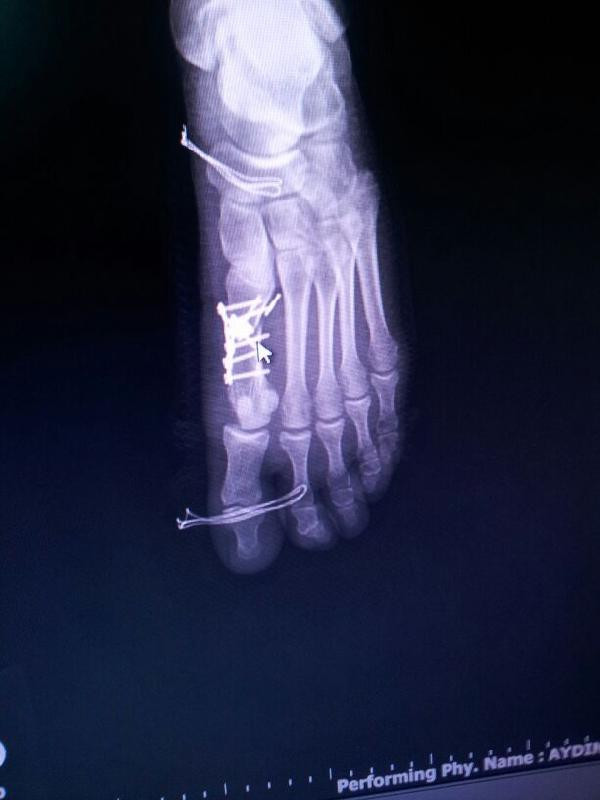

Bir kurumda memur Büşra Nergiz, sol ayak başparmağının yanındaki parmakta hissettiği ağrı nedeniyle, Yalova Devlet Hastanesi Ortopedi ve Travmatoloji Bölümü'nde Opr. Dr. Özgür A'ya muayene oldu. Ağrı hissettiği parmakta kırık saptanarak ameliyata alınan Nergiz'in, iddiaya göre yanda sağlam olan başparmağına operasyon yapıldı ve 5 platin takıldı. Nergiz, şikayetçi olarak suç duyurusunda bulundu. İdari soruşturma başlatan İl Sağlık Müdürlüğü de doktoru açığa aldı.

Hastanın ifade ettiği üzere 2. parmakta eski bir kırığı olup 1. parmağı gelip bunun üzerine binmektedir. Böylece 2. parmakta çekiç parmak oluşmuştur. Dikkatli bir ölçümde, açıların normal sınırların üstünde olduğu görülmektedir. Medyada olan, üzerine basmadan çekilen grafisinde dahi, en uç noktada yumuşak dokuların üst üste geldiği gözlenmektedir. Hastaya, ayak 2. parmağa yönelik bir düzeltmenin sorunu gidermeyeceği, 2. parmağın 1. parmak altına daha fazla gireceği, cerrahi müdahalenin 1. parmağa olması gerektiği açık bir şekilde anlatıldı.

Hasta, anlatılan şekilde ameliyat olmayı kabul etmiştir. Başarılı geçen ameliyat sonrasında hasta, müvekkilime teşekkür ederek hastaneden ayrılmıştır. Bu bağlamda müvekkilim, hakkında yapılan bu kara propaganda karşısında Cumhuriyet Başsavcılığı’na başvuracak olup bu davanın takipçisi olacaktır."